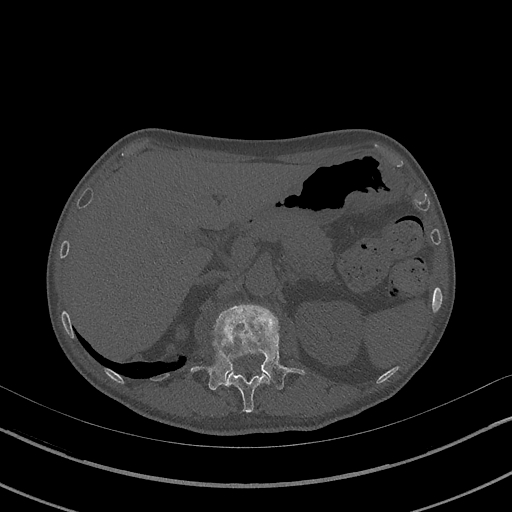

For the Covid-19 infection segmentation task, we evaluated both binary and multi-class segmentation tasks, as summarized in Table 1. Dataset_1 RADIOLOGISTS (2019) consists of 100 slices showing Covid-19 infection, including lungs and multi-class infection masks (GGO and Consolidation). Dataset_2 RADIOLOGISTS (2019) comprises nine 3D CT scans, totaling 829 slices, with 373 slices indicating Covid-19 infection. Expert radiologists labeled this dataset, providing masks for lungs, binary infection (non-infected and infected), and multi-class labels (non-infected, GGO, and Consolidation).

For the binary segmentation task, we divided Dataset_2 into 70%-30% splits for training and testing, respectively. For the multi-class segmentation task, we used Dataset_2 and 50% of Dataset_1 (50 slices) for training, while the remaining 50 slices of Dataset_1 were used for testing. Table 2 summarizes the number of slices for the GGO and Consolidation classes in both the training and testing splits. As shown in the table, the limited number of slices for each class presents a significant challenge for multi-class segmentation.

The four visualized examples in Figure 6 are from the binary segmentation experiments of Dataset_2. The first example shows a case in which infection has spread to both lungs and appears as a GGO and small consolidation region at the bottom of the right lung. The comparison between the Unet++ mask and the ground truth (GT) shows that the Unet++ architecture fails in segmenting most of the infection regions. The CopleNet, MISSFormer and UCTransNet masks show improved segmentation performance compared to Unet++. However, these architectures still miss some infected regions or segment lung tissues as infection instead. The mask of our proposed approach shows high similarity with GT in term of the number of regions and their global shape. Both examples 2 and 3 are cases where the infection has a peripheral distribution. The visualized masks show that the proposed D-TrAttUnet is the best architecture consistent with the ground truth. The fourth example depicts a severe case where the infection has spread to most of the lung regions. The visualized masks exhibit that our proposed architecture performs better than the comparison architectures.

Slice Unet++ CopleNet MISSFormer UCTransNet D-TrAttUnet GT

Figure 6: Visual comparison of a segmentation model trained with different segmentation architectures for Binary Covid-19 segmentation using Dataset_2 and Dataset_3.